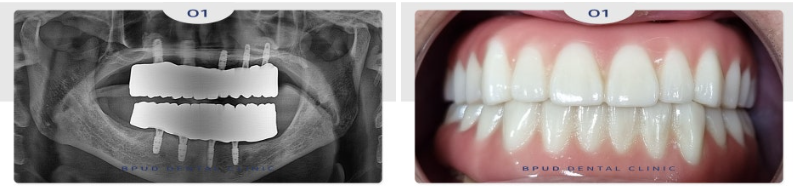

오늘은 매직 4를 이용한 임플란트 틀니로

기능과 심미성 모두를 회복하신

환자분을 소개해 드리려고 합니다.

환자분께서는 50대 남성분으로

위, 아래 치아가 대부분 없는 상태로

임플란트 상담을 위해 부평치과 잘하는곳

부평유디치과에 내원해 주셨는데요.

임플란트를 식립하고

3개월 후의 사진입니다.

약 4개월 후 최종 보철물까지

마무리를 하였는데요.

부평치과 부평유디치과

정기검진 내원 시 사진입니다.

기존의 틀니보다 훨씬 편하고

심미적이며, 식사도 잘 하시게 되어

환자분의 만족도도 매우 높았습니다.